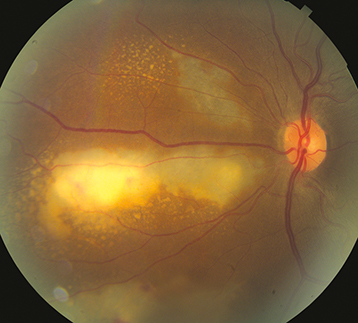

CMV is the most frequent ocular opportunistic infection in patients with AIDS, but is 80% to 90% less common in the era of ART. CMV is almost never seen unless the CD4+ count is <100 cells/mm3. Because active retinitis is often asymptomatic, patients with CD4+ counts <100 cells/mm3 should be seen at least every 3 to 6 months. May also be seen in other immunocompromised states (e.g., leukemia and post-transplant patients). Local ocular immunosuppression (intraocular and periocular steroid injections) may precipitate CMV retinitis in otherwise healthy patients.

Scotoma or decreased vision in one or both eyes, floaters, or photopsias. Pain and photophobia are uncommon. Often asymptomatic.

Anterior uveitis with nongranulomatous, stellate KP almost always present but mild. Vitritis is usually mild. RPE atrophy and pigment  clumping result once the active process resolves. Rhegmatogenous retinal detachment (RRD) occurs in approximately one-third of patients with CMV retinitis with increased risk when >25% of the retina is involved.